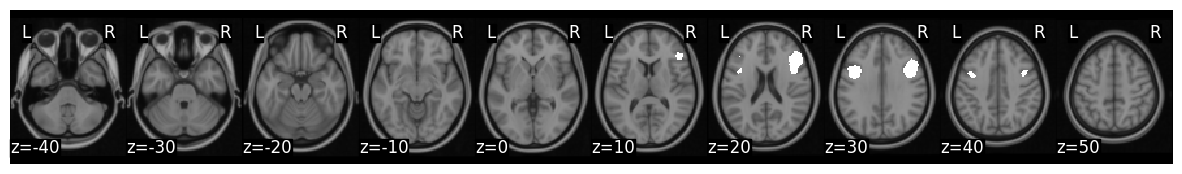

Mask is s k=50 whole brain parcellation based on neurosynth coactivations. Target ROIs correspond to left and right somatomotor cortex

mask = Brain_Data(os.path.join(get_resource_path(), 'k50_2mm.nii.gz'))

mask_x = expand_mask(mask)

mask_x[27].plot()